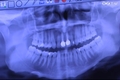

Innováció a fogászatban

2012. január 16., 23:30

Az Új Széchanyi terv keretében 2012 januárjától lehet pályázni az Innováció a fogászatban elnevezésű pályázatra, melynek célja a fogászati szektorban működő innovatív mikro-, kis- és középvállalkozások ...